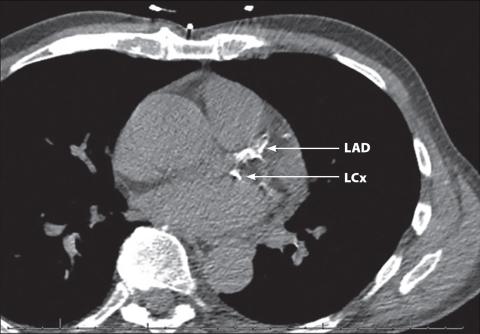

Sample coronary artery calcium scoring CT scan.

Early detection, lasting prevention: The significance of coronary artery calcium scores

Atherosclerosis, a type of chronic inflammation that is marked by the buildup of lipid-rich plaque within the walls of the arteries, is the leading cause of cardiovascular disease, including coronary artery disease,... Read More